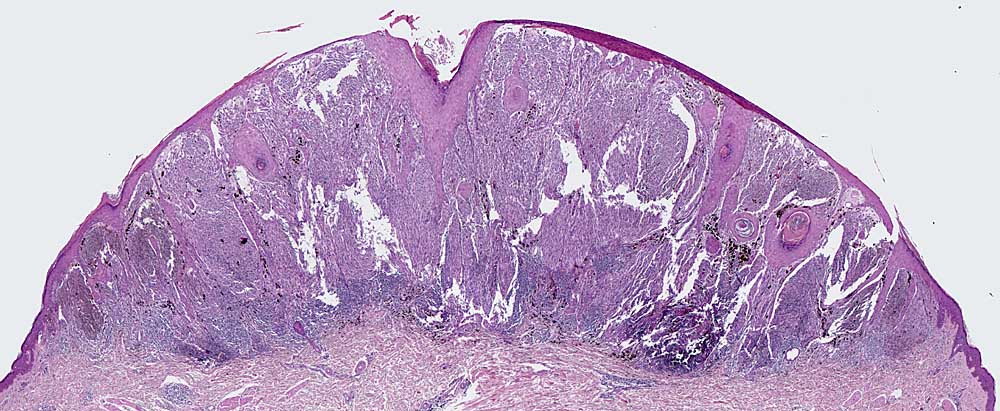

spitzoides Melanom

maligner Tumor

Haut, Kopf

Haut

Auffallend symmetrischer Tumor aus spindeligen Tumorzellen. Auf den ersten Blick erinnert die Läsion an einen Spitz Naevus. Die Pigmentverteilung ist jedoch asymmetrisch, die Tumorzellen bilden sehr zellreiche expansive Faszikel ohne dazwischenliegendes Stroma, die Epidermis ist fokal verdünnt.

Nachweis zahlreicher Mitosen

25

44

männlich